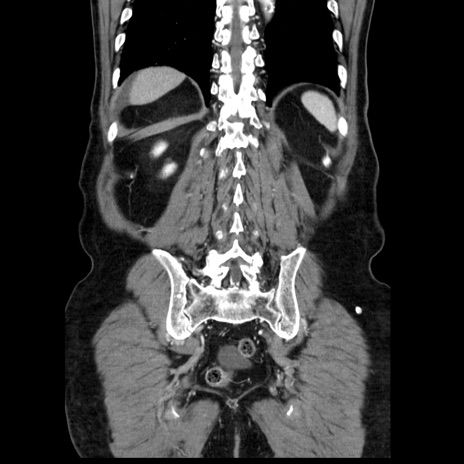

症例30(冠状断像)

【症例】80歳代男性

【主訴】臍周囲痛

【現病歴】約6時間前から臍下部痛が出現。次第に腹部膨隆・背部痛も生じてきたため来院。背部痛の場所は変化しない。

【既往歴】腎盂腎炎

【身体所見】意識清明、BT 36.3℃、BP  131/87mmHg、P 87bpm、SpO2 100%(RA)、臍周囲自発痛・圧痛あり、反跳痛なし、自発痛部位に一致して板状硬あり、腹部膨隆、腸雑音減弱、CVA tenderness両側陰性。

【データ】WBC 19600、CRP 0.33